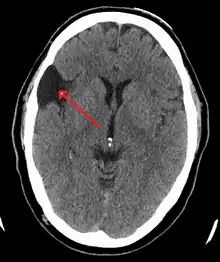

Diagnosis is principally by MRI. Frequently, arachnoid cysts are incidental findings on MRI scans performed for other clinical reasons. In practice, diagnosis of symptomatic arachnoid cysts requires symptoms to be present, and many with the disorder never develop symptoms.